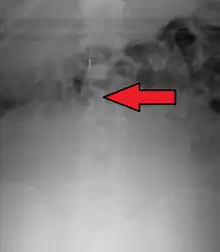

An inferior vena cava filter is a medical device made of metal that is implanted by vascular surgeons or interventional radiologists into the inferior vena cava to prevent a life-threatening pulmonary embolism (PE) or venous thromboembolism (VTE).[2][3]

The filter is designed to trap a blood clot and prevent its travel to the lung where it would form a pulmonary embolism.[4][3] Their effectiveness and safety profile is well established, and they may be used when anticoagulant treatment is not sufficient.[5]